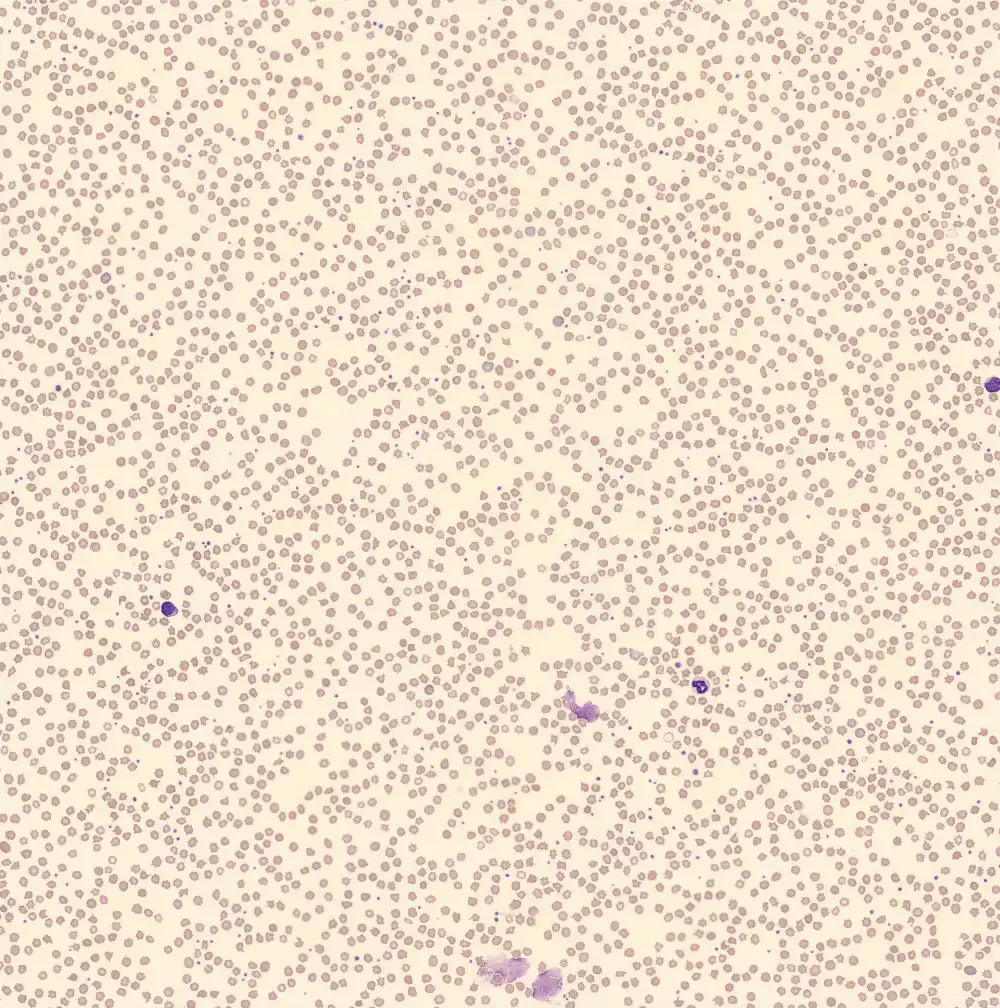

Peripheral blood

The peripheral blood contained overtly small, abnormal erythrocytes; particularly echinocytes. Hemoglobin was

6.2 mmol/L

and MCV was 54 fL

which in humans may well fit iron deficiency or a hemoglobinopathy. The large amount of echinocytes is an artifact; the cell membrane contains relatively more cholesterol and has a different distribution of various phospholipids (especially saturated fatty acids) compared to humans. This different composition makes the erythrocyte of a pig a lot more sensitive to dehydration artifacts and effects of EDTA.Neutrophils

The neutrophils, as the WDF channel suggested, are hypogranular. The nuclear segmentation is a lot less defined than usual in humans. For a pig this is perfectly normal; in a human this may fit with myelodysplasia.

Lymphocytes

The lymphocytes show strong similarity to those of humans. However, the lymphocyte count is high at 60% within a total leukocyte count of

16⋅109/L

.Monocytes

The monocytes are remarkably small compared to human monocytes. However, pig monocytes do exhibit similar blue-pink cytoplasm with some fine granules.

Basophils

This basophil appears to show some hyposegmentation. However, only one basophilic granulocyte was present making this an incidental finding.

Eosinophils

The eosinophilic granulocytes are very similar to those of humans.